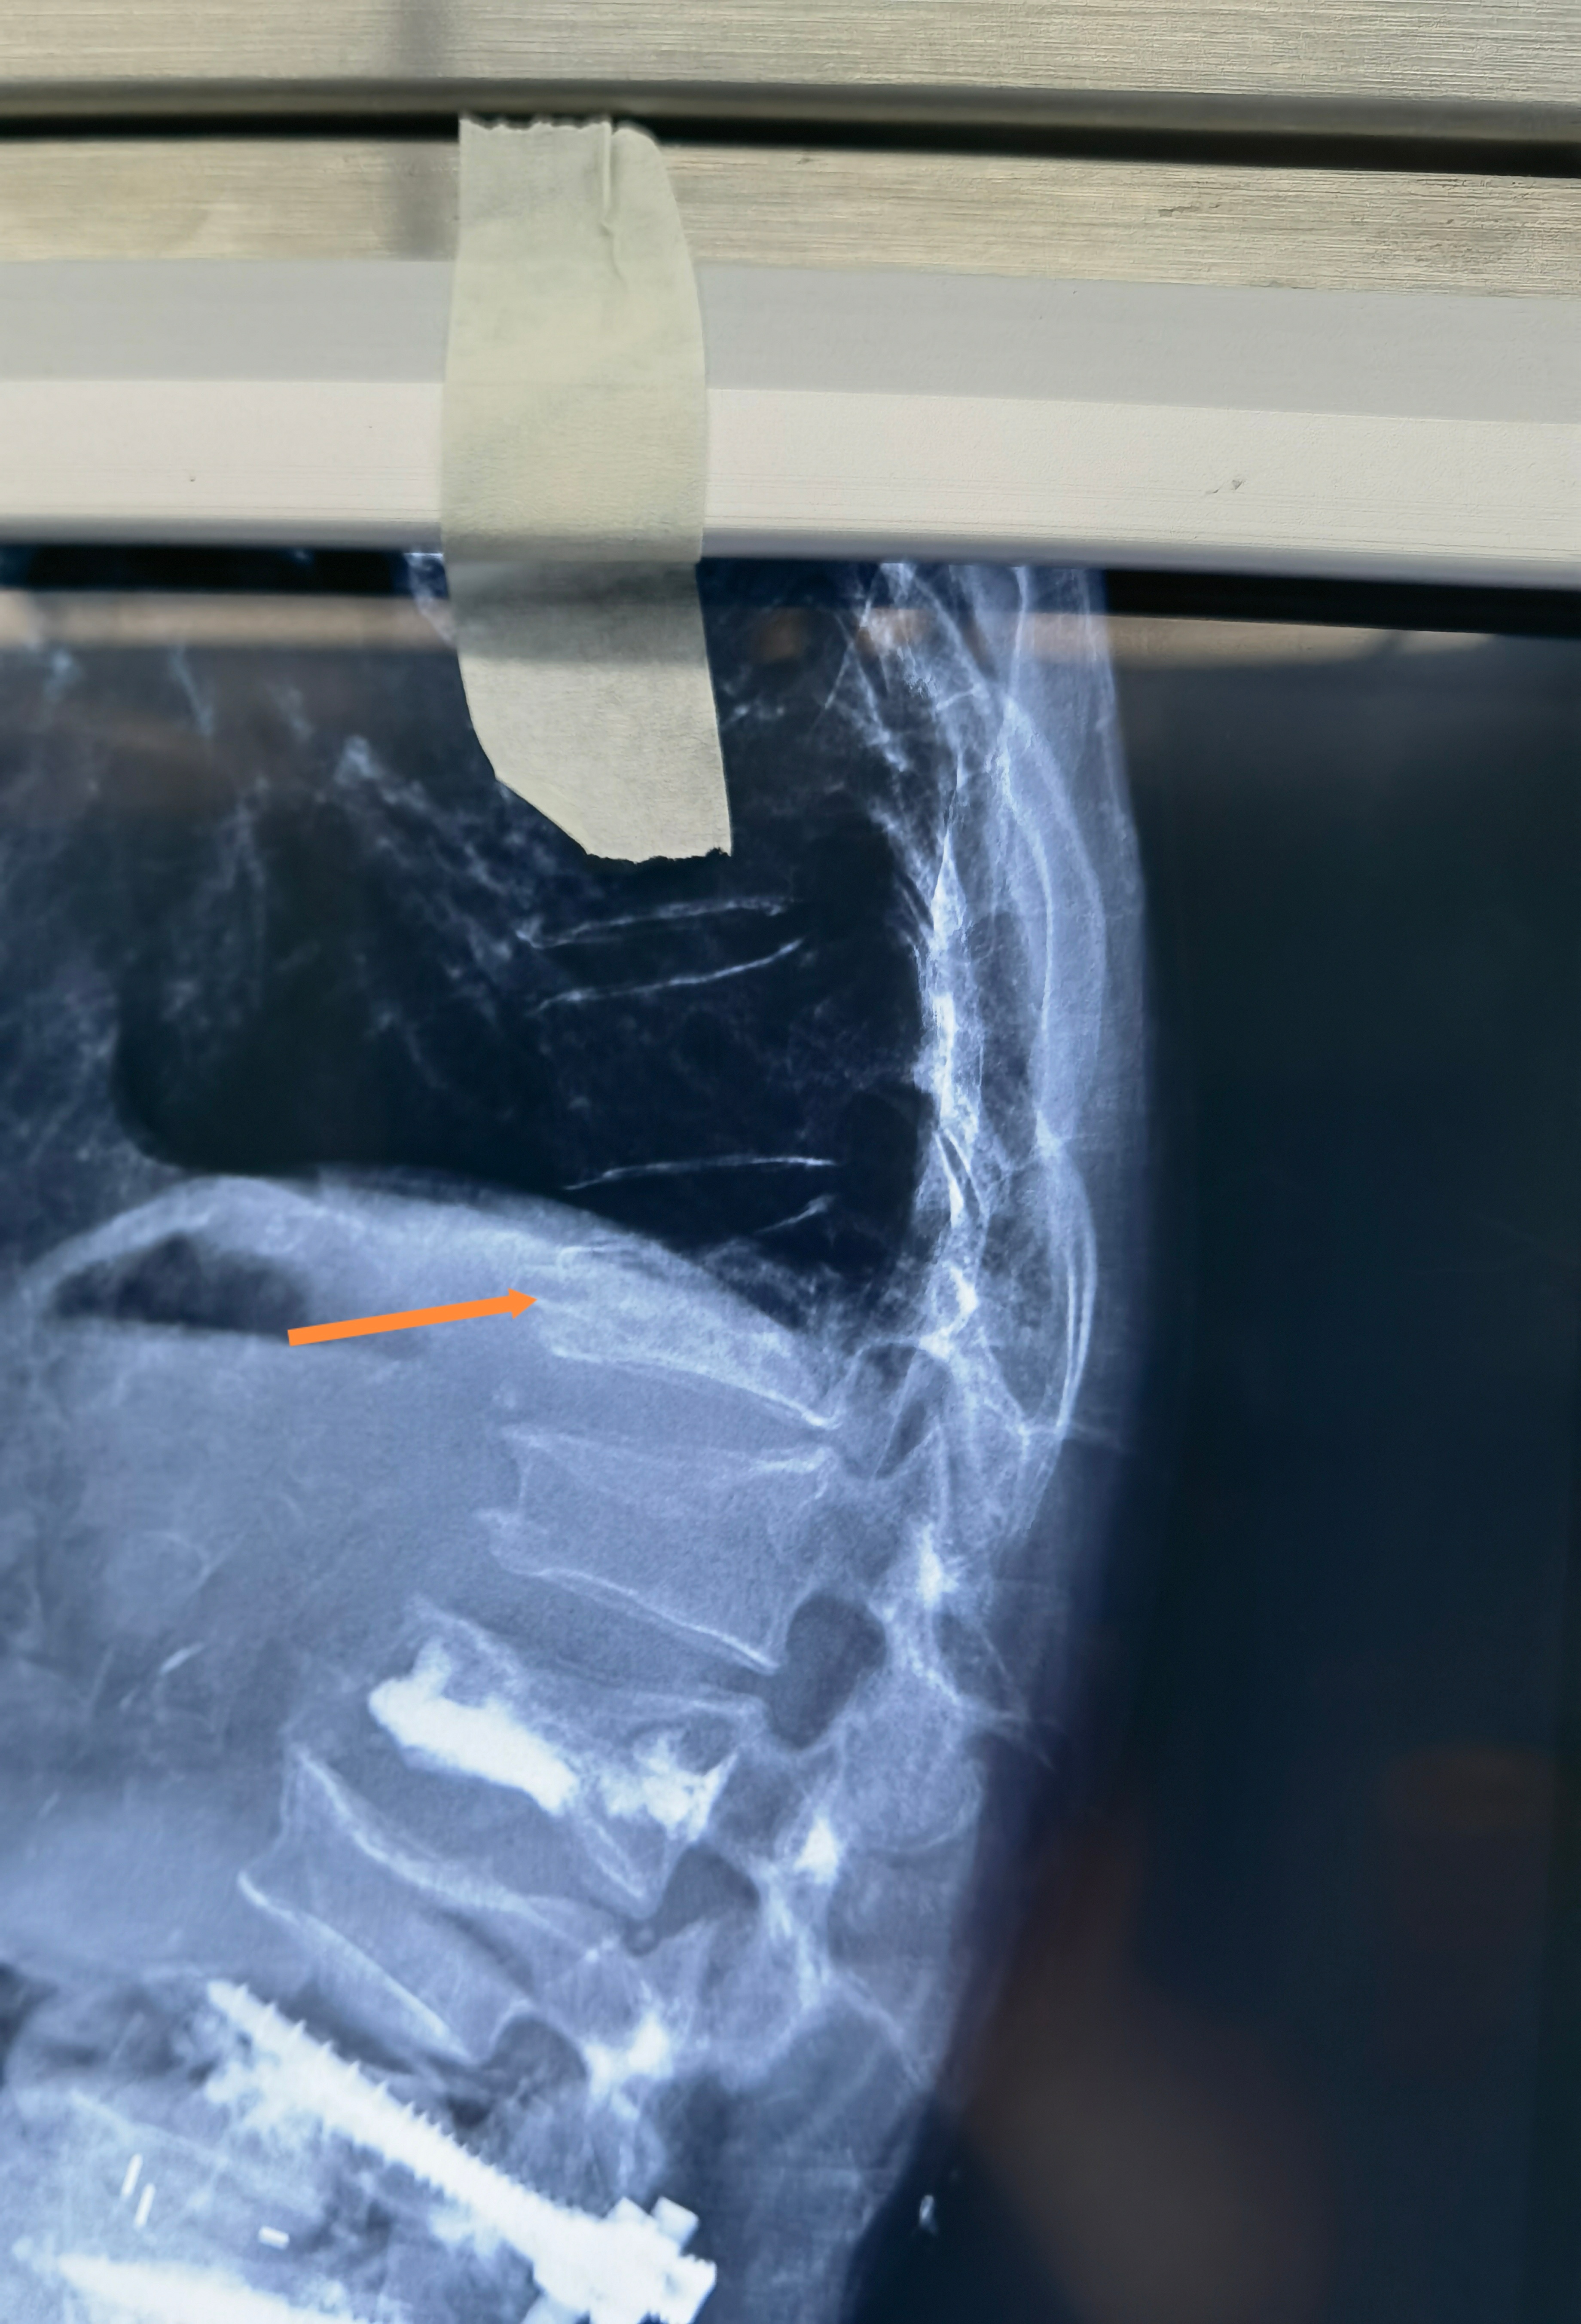

老人家的脊柱骨折首选微创手术,不建议保守治疗。看这个老太太,躺着做CT显示胸12椎体高度可,但是骨头里面有一个很大的空洞。站着拍片子这个椎体明显变矮了。这就是很恐怖的一种不稳定脊柱骨折。我们局麻注射骨水泥,注射了将近20毫升,这是极限操作,目的是把大空洞完全填满,把骨头撑起来,消灭不稳定。如果稍微少填一点,可能手术后还是不稳定,就会再骨折。这种极限操作的风险是很高的,水泥有可能漏到神经周围,导致病人瘫痪。所以大部分医生会选择做大手术,钉棒固定。